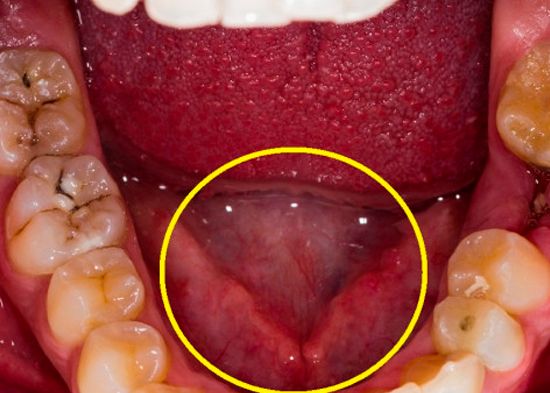

Los síntomas más comunes son: la aparición de aftas, llagas, ampollas dolorosas que se forman en la boca cuando la infección está activa, es posible contraerla si al besar tienes una herida abierta, por sexo oral, anal o genital.

Se trata de una infección bacteriana que se transmite por contacto sexual, en la boca, a través de una llaga abierta al realizar sexo oral, con menor frecuencia, al besar a una persona contagiada por la misma situación: una herida abierta en la boca con besos profundos o prolongados.